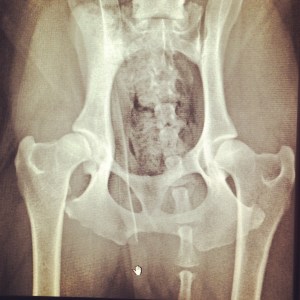

Bubba has been giving Beary LOADS of extra love and today I went to talk to our vet. He has hip dysplasia in his right hip. And he will, at some point in the unknown future, need a hip replacement. Which is not a small or cheap operation. At the moment we’re treating him with meds and anti-inflammatories. Our vet wants to see how he goes on these first, and is of the opinion they will buy us some time. Unless he does something to aggravate it. So rambunctious games of bitey face with Bella will need to be reigned in.